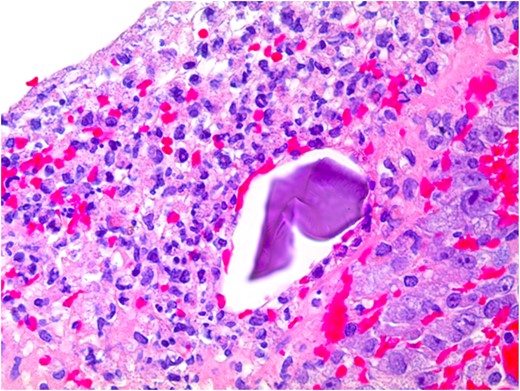

At pathological examination, the mucosa was diffusely hemorrhagic with extensive multifocal ulcerations. Crystalloid particles consistent with Kayexalate were identified throughout the bowel wall (Figs 1 and 2). There was no evidence of neoplasia or viral inclusions and cytomegalovirus immunostains were negative. Thus, a diagnosis of kayexalate-induced colon ischemia and necrosis was made.

Colonic ulceration with necrosis and kayexalate crystal identified.

The presence of kayexalate crystals on pathology specimens distinguishes kayexalate-induced necrosis from ischemic necrosis. Otherwise, these entities have a similar presentation. Identification of rhomboid or triangular, basophilic crystals with a mosaic pattern on hematoxylin and eosin (H & E) stain is pathognomonic for the presence of kayexalate (Figs 1 and 2). These crystals are identified adherent to the mucosa or imbedded within inflammatory milieu and ulceration [10].